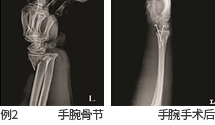

- 检查的目的 : 观察人体解剖学构造,观察骨骼上是否有骨节, 确认软组织是否存在异常,观察患病部位的进程。

- 检查部位 : 头颈部, 胸部, 腹部, 骨骼系统, 小儿摄影等全身摄影